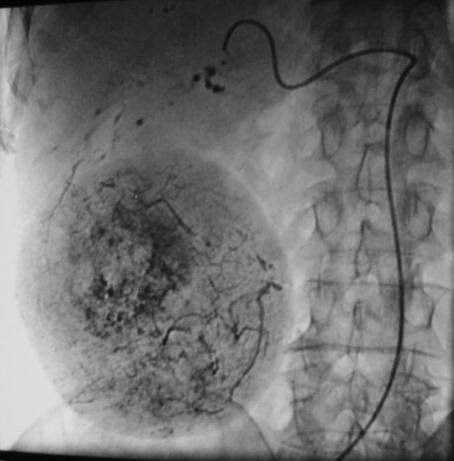

当肿瘤比较局限,导管可以前进至段或者亚段动脉,从而只对存在肿瘤区域进行化学栓塞。使用这项技术时推荐使用共轴的微导管。整体肿瘤区域是否完全被导管栓塞可以从动脉造影中估计,但是,从导管内注入造影剂时进行动脉造影CT可以得到更准确的评价。

碘化油的量取决于肿瘤的大小和血管分布,导管置入部位,和肝功能受损情况。一般剂量为3至10毫升。在靶动脉内放置的导管内注射2%的利多卡因5ml后再进行化学栓塞注射。这样可以避免在操作过程中或操作刚结束时肝脏内产生的剧烈疼痛。然后,抗肿瘤药物与碘化油的混合物被缓慢注入。最后,被剪成小块状的明胶海绵或海绵颗粒或PVA与造影剂和少量的抗肿瘤药物的混合物注入肝动脉。如果存在肝外侧支动脉,则在此动脉中也应放置导管,进行化学栓塞。如果存在显著的动-门脉短路,则在注入碘化油乳剂前,应首先注入少量明胶海绵以阻断血流。动-肝静脉短路也应该被同样处理,但在注入碘化油之前寻找是否有到体循环的短路是最重要的,避免肝动脉栓塞后的肺栓塞。 注入碘化油乳剂之后,应进行数字减影血管造影(DSA),从而确定肿瘤染色是否已经消失。术后定期应拍摄腹部X线片,以确定碘化油是否持续沉积。

完成碘油化疗性栓塞后,标准的随访程序并没有建立。但患者应随访肿瘤标记物和CT。早期的治疗反应是通过CT来评价的,一般在治疗后一周和一个月各进行一次。治疗反应于肿瘤内碘化油的储留关系密切。

一般栓塞后早期情况下肿瘤与碘油沉积有4种情况。满月型,半月型,弥散型和没有碘油储存的情况。当碘油满月型沉积在肝癌内,其储留时间为一个月或者更长,则肿瘤一般都坏死。半月型碘油沉积说明栓塞不足或一部分碘油已经经瘤内的动静脉瘘分流。晚期出现的半月型或碘油内出血充盈缺损(结节内结节,Nodular in Nodular)则表明肿瘤可能复发。如果存在任何肿瘤残余或者复发。尽管该位置病变在螺旋动力CT可表现为高密度(例如,动脉期)。但由于碘化油的聚集使的肿瘤的内部状态很难从CT上观察,此时应该使用MRI增强。聚集的碘化油并不影响MRI信号,因此活动性肿瘤可以通过MRI早期发现。 弥散型碘油沉积和根本就没有碘油沉积预示预后不良,特别是没有其它辅助治疗的情况下。诊断错误也应在考虑范围内,如不是原发性肝癌,而是胆管癌或其它少血管肝内肿瘤。